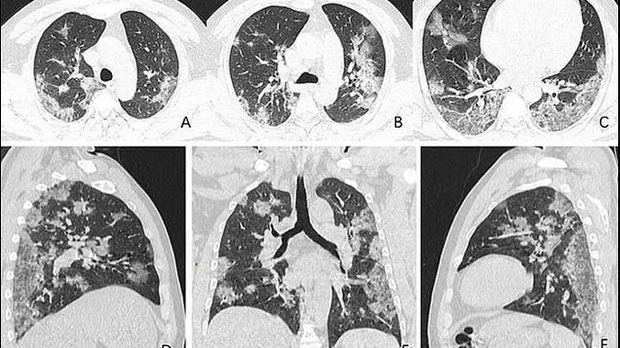

Na snimcima se vide bijele, razgranate sjenke u donjim uglovima pluća, što ukazuje na ono nešto što radiolozi zovu “neprovidno staklo” – djelimično ispunjene vazdušne prostore. Takve abnormalnosti slične su onima pronađenim kod pacijenata koji su imali SARS ili MERS, piše “Dejli mejl”.

Na snimcima se vidi kako je tečnost u vazdušnim prostorima njegovih pluća postala izraženija tokom vremena, što se vidi poređenje slika (A-F). Preminuli Kinez je primljen u bolnicu 25. decembra prošle godine, nakon što je trpeo kašalj i groznicu skoro dve nedelje. Dijagnostikovali su mu upalu pluća i akutni respiratorni distres sindrom (ARDS). Uprkos tretmanu, čovek je umro nedelju dana kasnije.